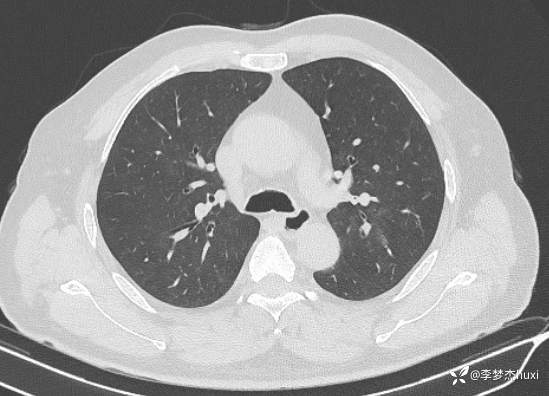

男性48岁,咯血3小时,咯血病因?

主诉:咯血3小时

简要病史:患者于入院前3小时无明显诱因出现咯血,为鲜红色,量较多,约10ml,伴胸闷、压气,伴咳嗽,无明显咳痰。

体格检查:T36.2℃,P110次/分,R20次/分,BP250/130mmHg。神清,呼吸平稳,浅表淋巴结不大,双肺叩清音,双肺未闻及干湿性啰音,心率110次/分,律齐,无杂音。腹部平坦,软,全腹无压痛,无反跳痛及肌紧张,肝脾肋下未触及,双下肢无水肿。

辅助检查:胸部CT:双肺炎症,双肺纹理增多,主动脉及冠状动脉钙化,主肺动脉稍增粗,右侧肾上腺点状高密度影,考虑脂肪肝。

临床诊断:肺炎咯血